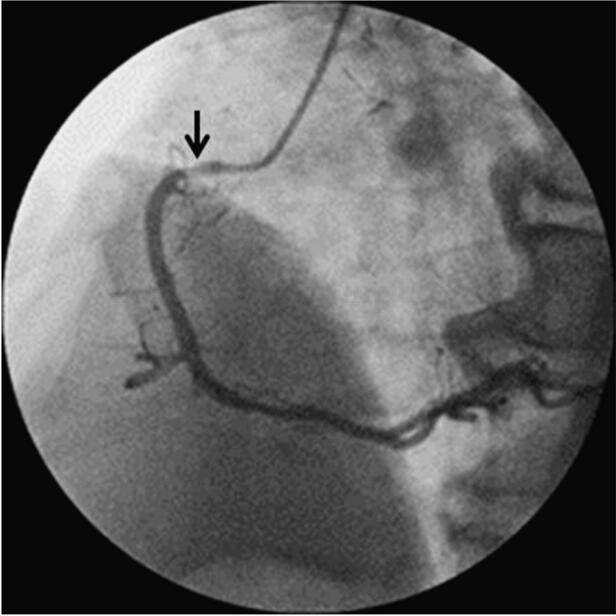

1月30日冠脉造影示:左主干远段狭窄50%,LAD开口狭窄95%,中段狭窄90%,可见血栓影像;LCX开口狭窄40%,远段节段性狭窄80%;钝缘支近段狭窄70%;RCA开口狭窄70%。患者于1月31日转至胸心外科行左内乳动脉‐前降支旁路移植手术。于2月10日行RCA开口支架置入(图068‐1~图068‐5,病变处标以箭头)。

图068‐4 RAO45°

右冠开口置入药物洗脱支架1枚:Cordis Cypher Select Plus 3﹒5 mm×23mm(图068‐6、图068‐7)。